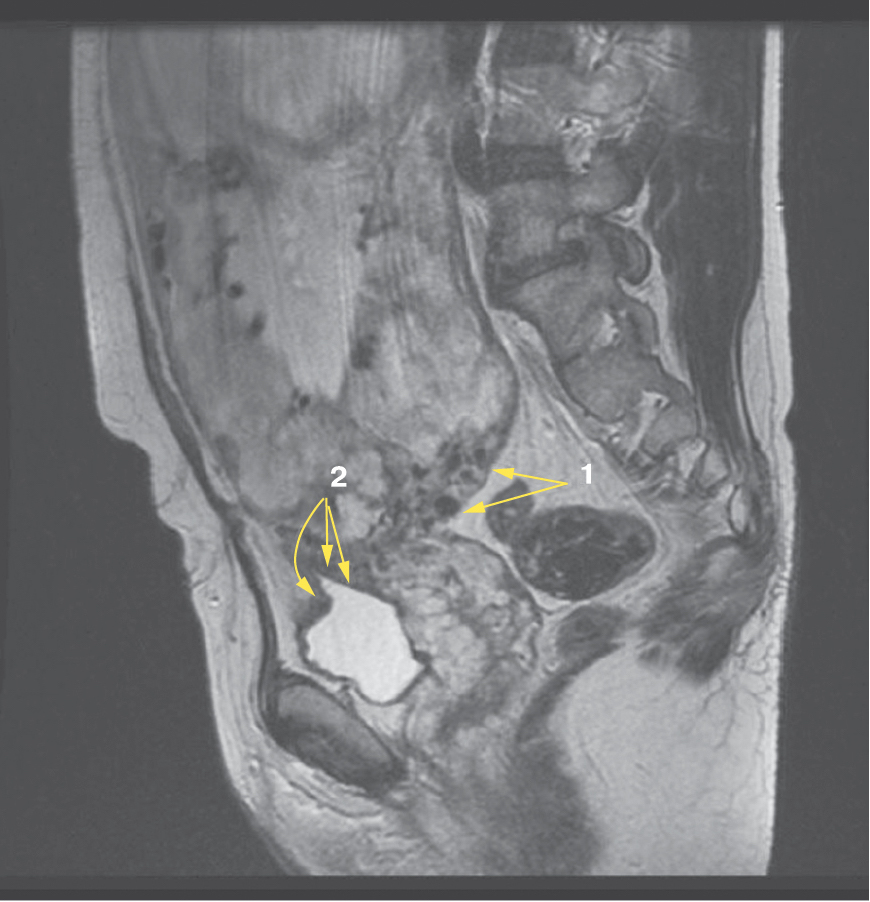

Также стоит выделить особый тип плацентарной гиперваскуляризации, а именно включение в плацентарной ткани изменений по типу «обнаженного сосуда» (рис. 1, 2). Мы провели анализ встречаемости данного признака среди наших пациентов. Любопытным наблюдением явилось то, что данный симптом в нашей выборке встречался только при наличии placenta percreta – 6 случаев, а именно при поражении параметриев, и не встречался при плацентарной инвазии, ограниченной миометрием. «Мостовидные сосуды» были менее специфичны, тем не менее, их наличие также сопровождало тяжелые формы врастания, обусловленные более глубокой инвазией ворсин хориона, – 8 случаев.

Рис. 2. МРТ placenta percreta, симптом «обнаженного сосуда»

Является ли симптом «обнаженного сосуда» патогномоничным для параметральной инвазии или нет, еще предстоит выяснить; однако в ходе исследования установлена его связь с частотой гистерэктомий в группах с наличием симптома «обнаженного сосуда», что, вероятно, обусловлено мощной сосудистой сетью коллатералей и неоангиогенезом. Во всех случаях обнаружения данного признака впоследствии была выполнена вынужденная гистерэктомия (рис. 3–6, пациентка Н., 37 лет).

Рис. 5. Корональная проекция МРТ. 1 – интрамуральная гиперваскуляризация; 2- измененный контур мочевого пузыря